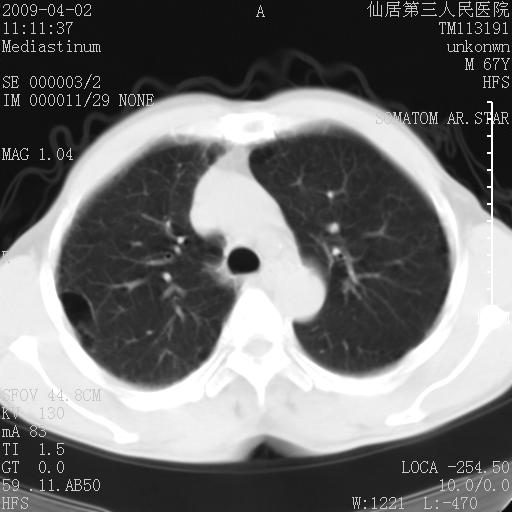

患者老年男性,乏力畏寒来诊,摄胸片示右下肺感染性病变,抗炎两周后复查胸片,无好转有进展。

后做ct平扫表现如下: